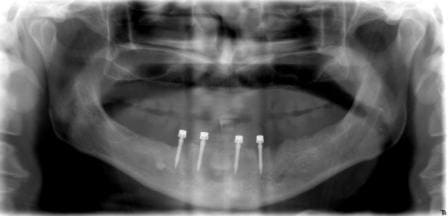

une mise en fonction immédiate à la mandibule sur 5 implants symphisaires astra, pas de recul parce que c'est frais de la journée.

mon correspondant a mis les implants et je me suis occupé de la prothèse.

rebasage de la prothèse totale provisoire sur des cylindres provisoires en titane connectés aux piliers défintifs avec suppression des extensions.

il était prévu de faire les empreintes pour le définitif dans la foulée mais comme on avait faim, je prendrais les empreintes le jour de la dépose des points.